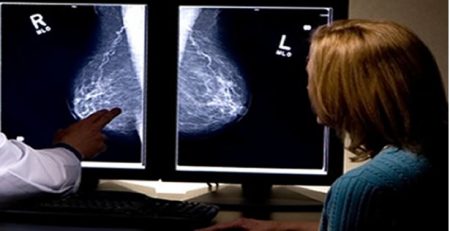

Radyologların aşırı iş yükü ve iş stresi, hatalı tanı olasılığını çok arttırıyor. Bunun kaçınılmaz sonucu gereksiz ya da hatalı tedaviler ya da büsbütün tedavisiz kalmak! .

Oysa radyoloğun görevi ve sorumluluğu, sanılanın aksine cihazları kullanmak değildir! Kesin tanıya götürecek şekilde bir tıbbi durumu açıklamaya yönelik yöntemleri belirlemek, bunları en etkin şekilde kullanmak ve ortaya çıkarılan bulguları yeterli, doğru ve tedaviye yol gösterici şekilde yorumlamaktır. Hastasını bilgilendirmek ve yönlendirmek ise radyoloğun en başta hekim olmasından kaynaklanan doğal görevidir!

Cihazın nasıl ve ne kadar verimli kullanılacağı tamamen radyoloğun bilgi, beceri ve deneyimine kalmıştır. Yani diğer tıp dallarında olduğu gibi radyolojide de işi insanlar yapar, cihazlar değil! İşte bu nedenle radyolojide KALİTE, cihaz faktörü kadar insan faktörüne de bağlıdır.